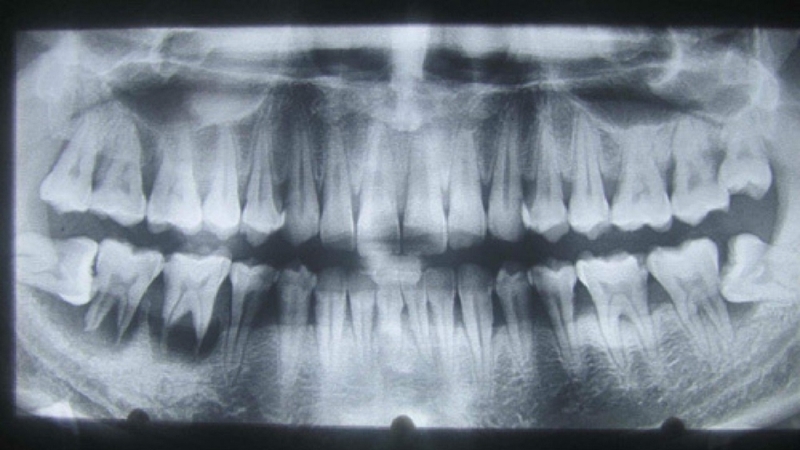

Đánh giá trạng thái răng khôn qua hình ảnh chụp CT trước khi nhổ răng khôn

Hình ảnh chụp CT răng có tác dụng rất lớn trong việc chẩn đoán, điều trị và theo dõi trong lĩnh vực nha khoa